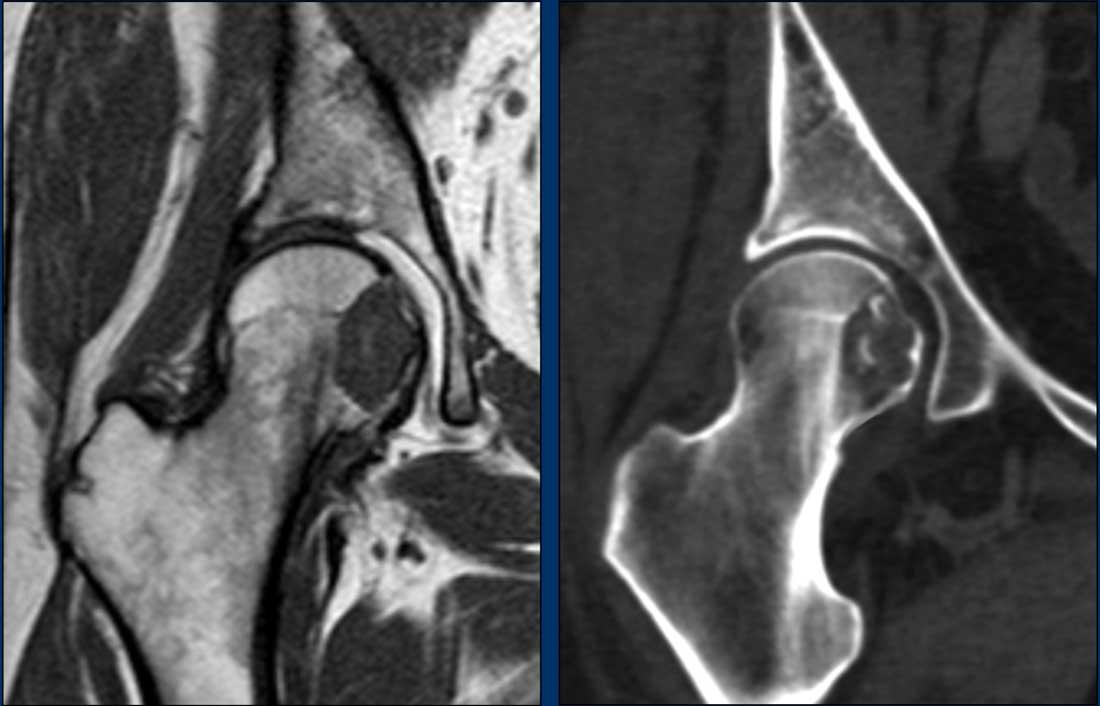

Hình ảnh

MRI chuỗi xung T1W mặt phẳng coronal cho thấy một tổn thương lệch tâm,

hơi giãn nở tại chỏm và cổ xương đùi phải.

Khó đánh giá liệu vỏ xương phía trong

chỉ bị mỏng hay đã bị phá hủy.

Do đó, CT không tiêm thuốc cản quang

đã được thực hiện bổ sung.

CT không tiêm thuốc cản quang cho thấy

tổn thương tiêu xương chứa các vôi hóa dạng chất nền sụn.

Có hình ảnh gặm mòn vỏ xương

phía trong, nhưng không có phá hủy vỏ xương.

Nạo vét được thực hiện để loại trừ u sụn dạng tế bào sáng. Đây là

một phân nhóm hiếm gặp của u sụn ác tính, xảy ra ở vùng đầu xương của xương dài ở

người trẻ tuổi.

Pathology diagnosis: ACT.